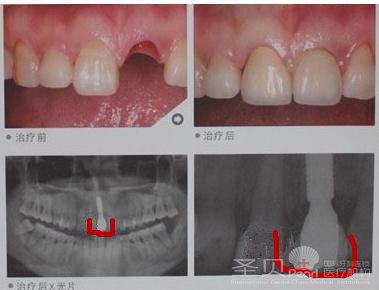

【病例简介】患者:王同学;年龄:18岁;牙症:前牙外伤脱落,未及时就诊,导致无法进行接牙治疗…【详细】 患者: 曹小姐 年龄: 31岁 牙症: 牙齿发生龋病,拔出残根,导致单颗牙齿缺失 检查: 前牙长时间缺…【详细】

患者: 曹小姐 年龄: 31岁 牙症: 牙齿发生龋病,拔出残根,导致单颗牙齿缺失 检查: 前牙长时间缺…【详细】 【病例简介】 患者: 李某某,女 年龄: 29岁 牙症: 5年前地砖上摔倒磕掉两颗门牙,两个门牙中间缺…【详细】